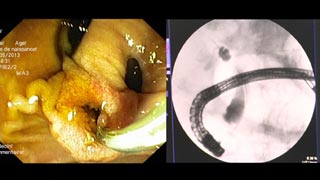

| Laparoscopic transgastric sphincterotomy for common bile duct stones

P Pessaux, J Huppertz, D Ntourakis, A Sportes, E Wedi, D Mutter, J Marescaux (France) |